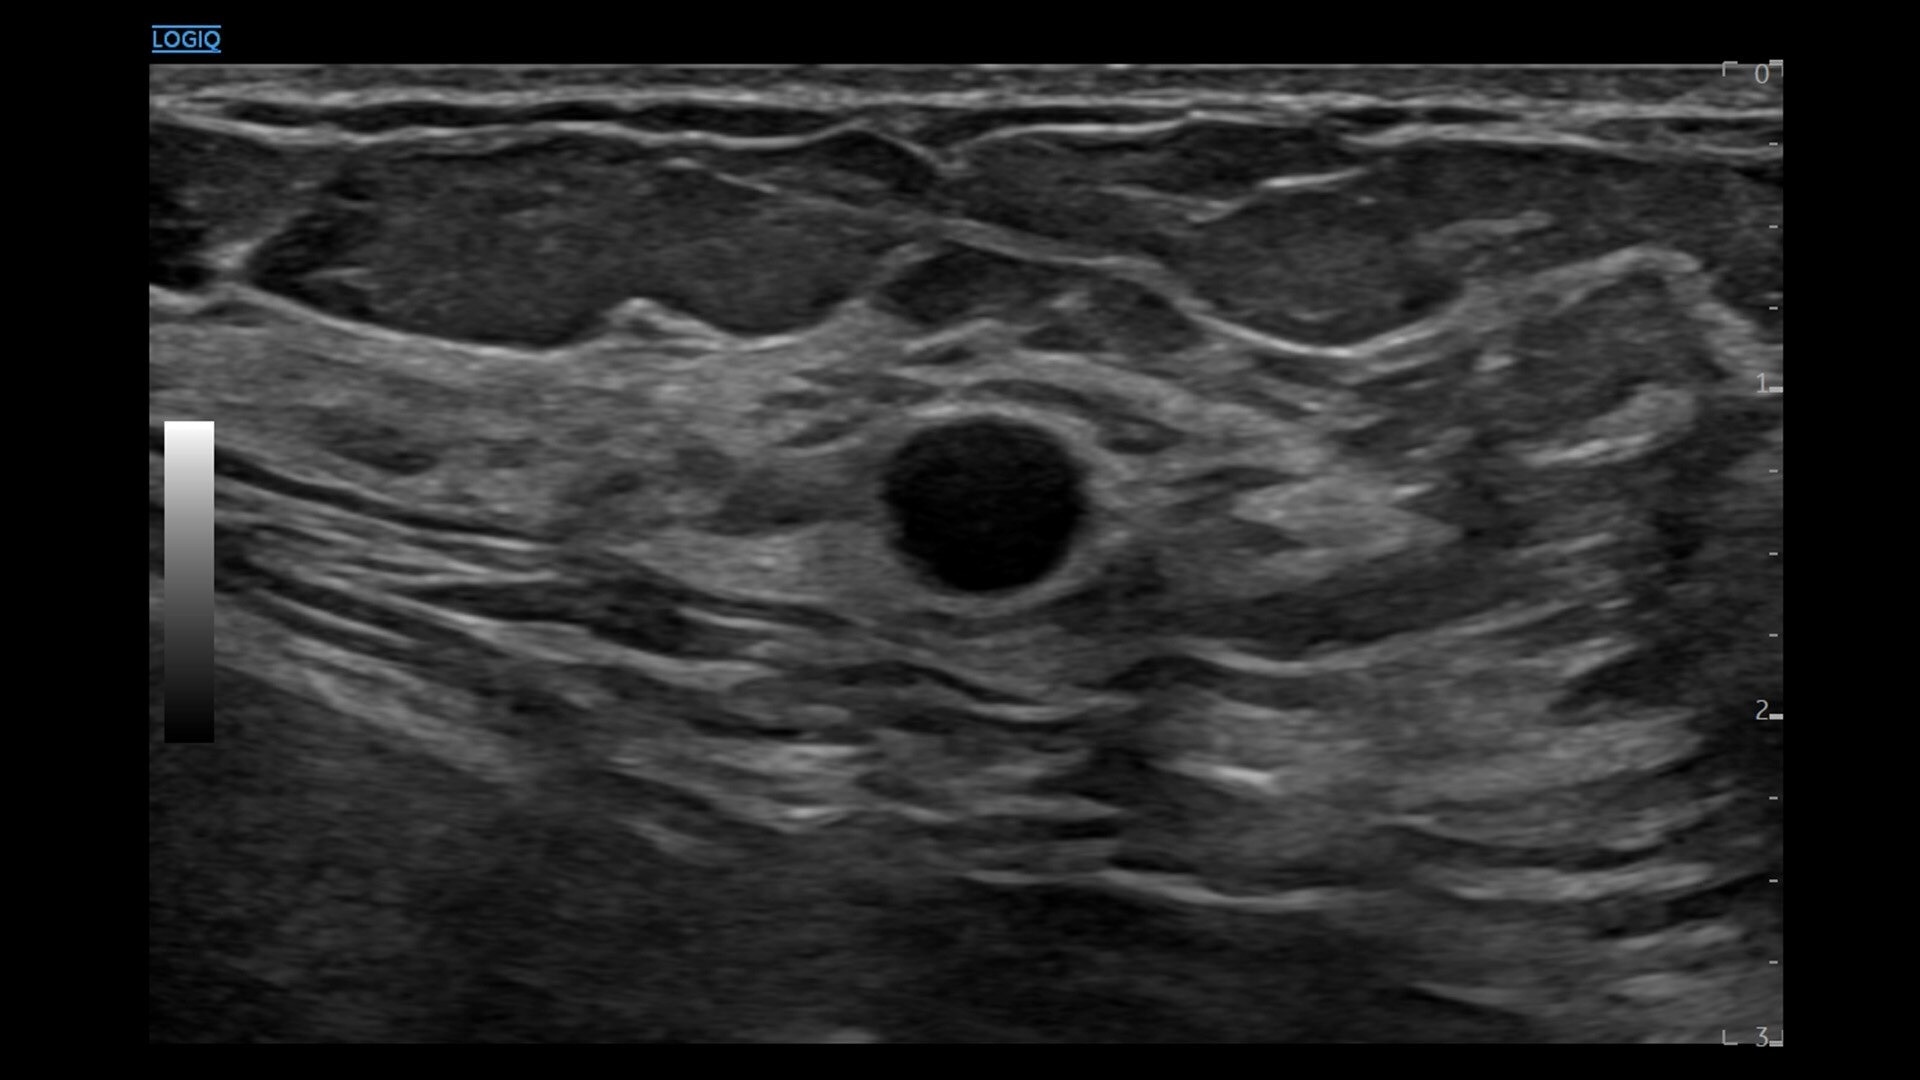

• New Auto Renal Measure Assistant: Automatically detects kidney and measures length, height and width in seconds*

• New SmartEdit: Shortcut keys enable segmentation-based editing capabilities in auto measurement tools, assisted by AI-based anatomy detection